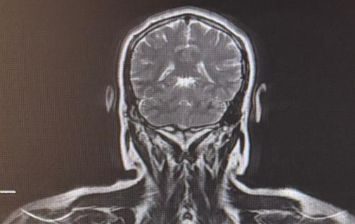

Ressonância Magnética

Dr Nacif possui treinamento avançado em ressonância magnética, desde desenvolvimento de sequências a suas aplicabilidades clínicas e consegue aplicar amplamente este conhecimento em todas as áreas deste incrível método. A possibilidade de realizar as os diversos avanços como estudos de perfusão, difusão, espectroscopia, mapeamento multiparamétrico em T1, T2 e T2*, avaliação de gordura e fibrose além dos estudos dinâmicos com cineRM. É possível também a realização de segunda leitura de exames já realizados focando em estudos diagnósticos de alta precisão ou até mesmo avaliações evolutivas de doenças ou tratamentos em específico.

10- Neuroimagem avançada